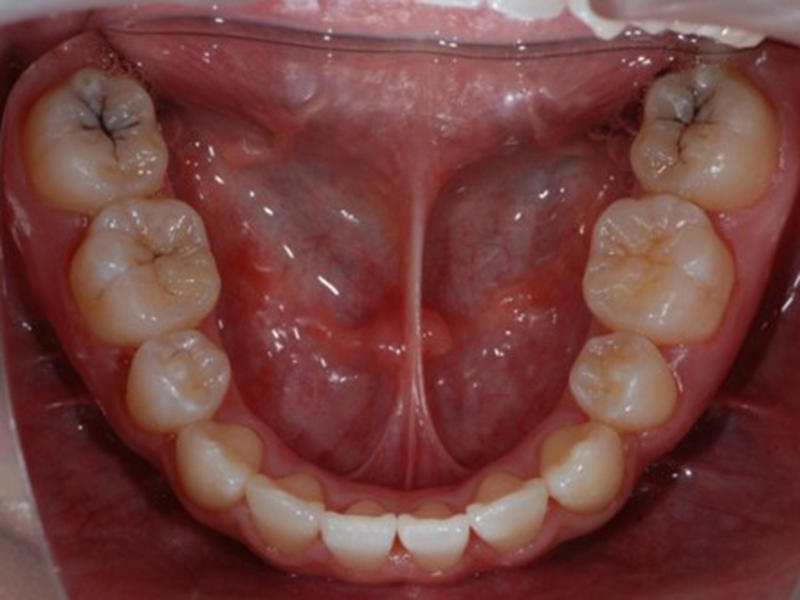

after